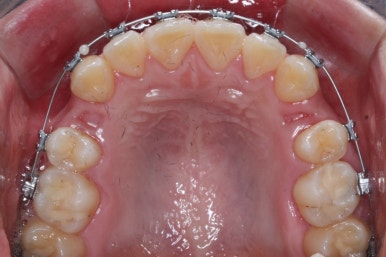

장치를 부착하였습니다.

부산교정전문의 키다리아저씨치과에서 이번에 사용한 장치는 메탈장치이며, 가장 기본적이고 역사가 오래된 장치가 되겠습니다.

우선 위쪽 작은 어금니 부터 발치하였습니다.

송곳니 바로 뒤쪽의 작은 어금니를 뽑은 것을 보실 수 있겠습니다.